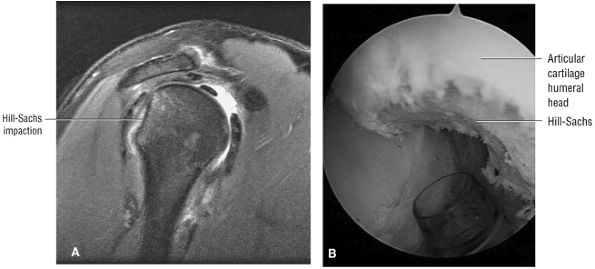

FIGURE 8.30 ● Axial images through the AC joint should be obtained on all shoulder MR examinations. (A) Axial T1- or PD-weighted images at this location are used to identify fractures of the distal clavicle and to demonstrate an os acromiale. (B) Axial FS PD-weighted images show cartilage covering the distal aspect of the clavicle and the medial aspect of the acromion at the AC joint. Cartilage defects and thinning, as well as subchondral bone marrow edema and cystic change, are evaluated on axial images through the AC joint. These degenerative changes can mimic the symptoms of a rotator cuff tear. (C) Axial T1- or PD-weighted images demonstrate the Hill-Sachs lesion of the humeral head, usually visualized as focal flattening or concave deformities in the posterolateral humeral head. The Hill-Sachs lesions is identified on the first or second superior axial image through the humeral head. Subcortical cystic change is more commonly visualized in the posterolateral humeral head and is usually an incidental finding in asymptomatic patients. (D) Axial FS PD-weighted images depict the biceps tendon coursing across the anteromedial aspect of the humeral head, within the rotator interval. This image location serves as a starting point for following the remainder of the biceps tendon into the bicipital groove on successive axial images moving from cranial to caudal. Tears of the supraspinatus and infraspinatus tendons are also identified at this image location on axial images. (E) Axial T1- or PD-weighted images allow evaluation of subcoracoid impingement. (F) In this location, thickening and increased signal in the superior glenohumeral ligament and coracohumeral ligament on an axial FS PD-weighted image may indicate adhesive capsulitis, particularly when accompanied by thickening and increased signal within the inferior glenohumeral ligament. (G) Axial T1- or PD-weighted images are used to identify subcortical cystic change in the greater and lesser tuberosity. This finding is commonly an indirect indication of abnormality or tearing in the overlying distal supraspinatus and subscapularis tendons, respectively. (H) Axial FS PD-weighted images through the proximal bicipital groove are used to identify “hidden lesions,” which are diagnosed when the biceps tendon is medially subluxing out of the bicipital groove, usually into a distal subscapularis tear or anterior to the lesser tuberosity. A degenerated biceps tendon may appear flattened and elongated as it rounds the lesser tuberosity into the proximal bicipital groove. Commonly, only the medial “tail” of the flattened degenerated biceps tendon subluxes out of the groove; the remainder of the flattened biceps tendon stays within the groove. (I) Axial T1- or PD-weighted images display the osseous glenoid subchondral surface, which should appear flat. Osseous glenoid remodeling, hypertrophy, deformity, subchondral cystic change, and edema are commonly identified as indirect evidence of overlying chronic cartilage degeneration or prior trauma. Posterior glenoid spurring may completely replace a degenerated or markedly attenuated posterior labrum. (J) Axial FS PD-weighted images are optimal for displaying the glenoid and humeral head cartilage. Chondral fissures, thinning, and defects are visualized when viewing successive cranial-to-caudal images through the glenohumeral joint. The anterior and posterior labrum are also optimally visualized and are normally firmly adherent to the glenoid and glenoid articular cartilage. (K) Axial T1- or PD-weighted images are used to identify bony Bankart lesions. These lesions are seen on inferior axial images through the glenohumeral ligament as oblique fracture lines extending through the anterior inferior glenoid. (L) Axial FS PD-weighted images show the prominent anterior band of the IGHL, which is occasionally mistaken for a tear of the anterior inferior labrum when fluid is interposed between the anterior band and the normal labrum.